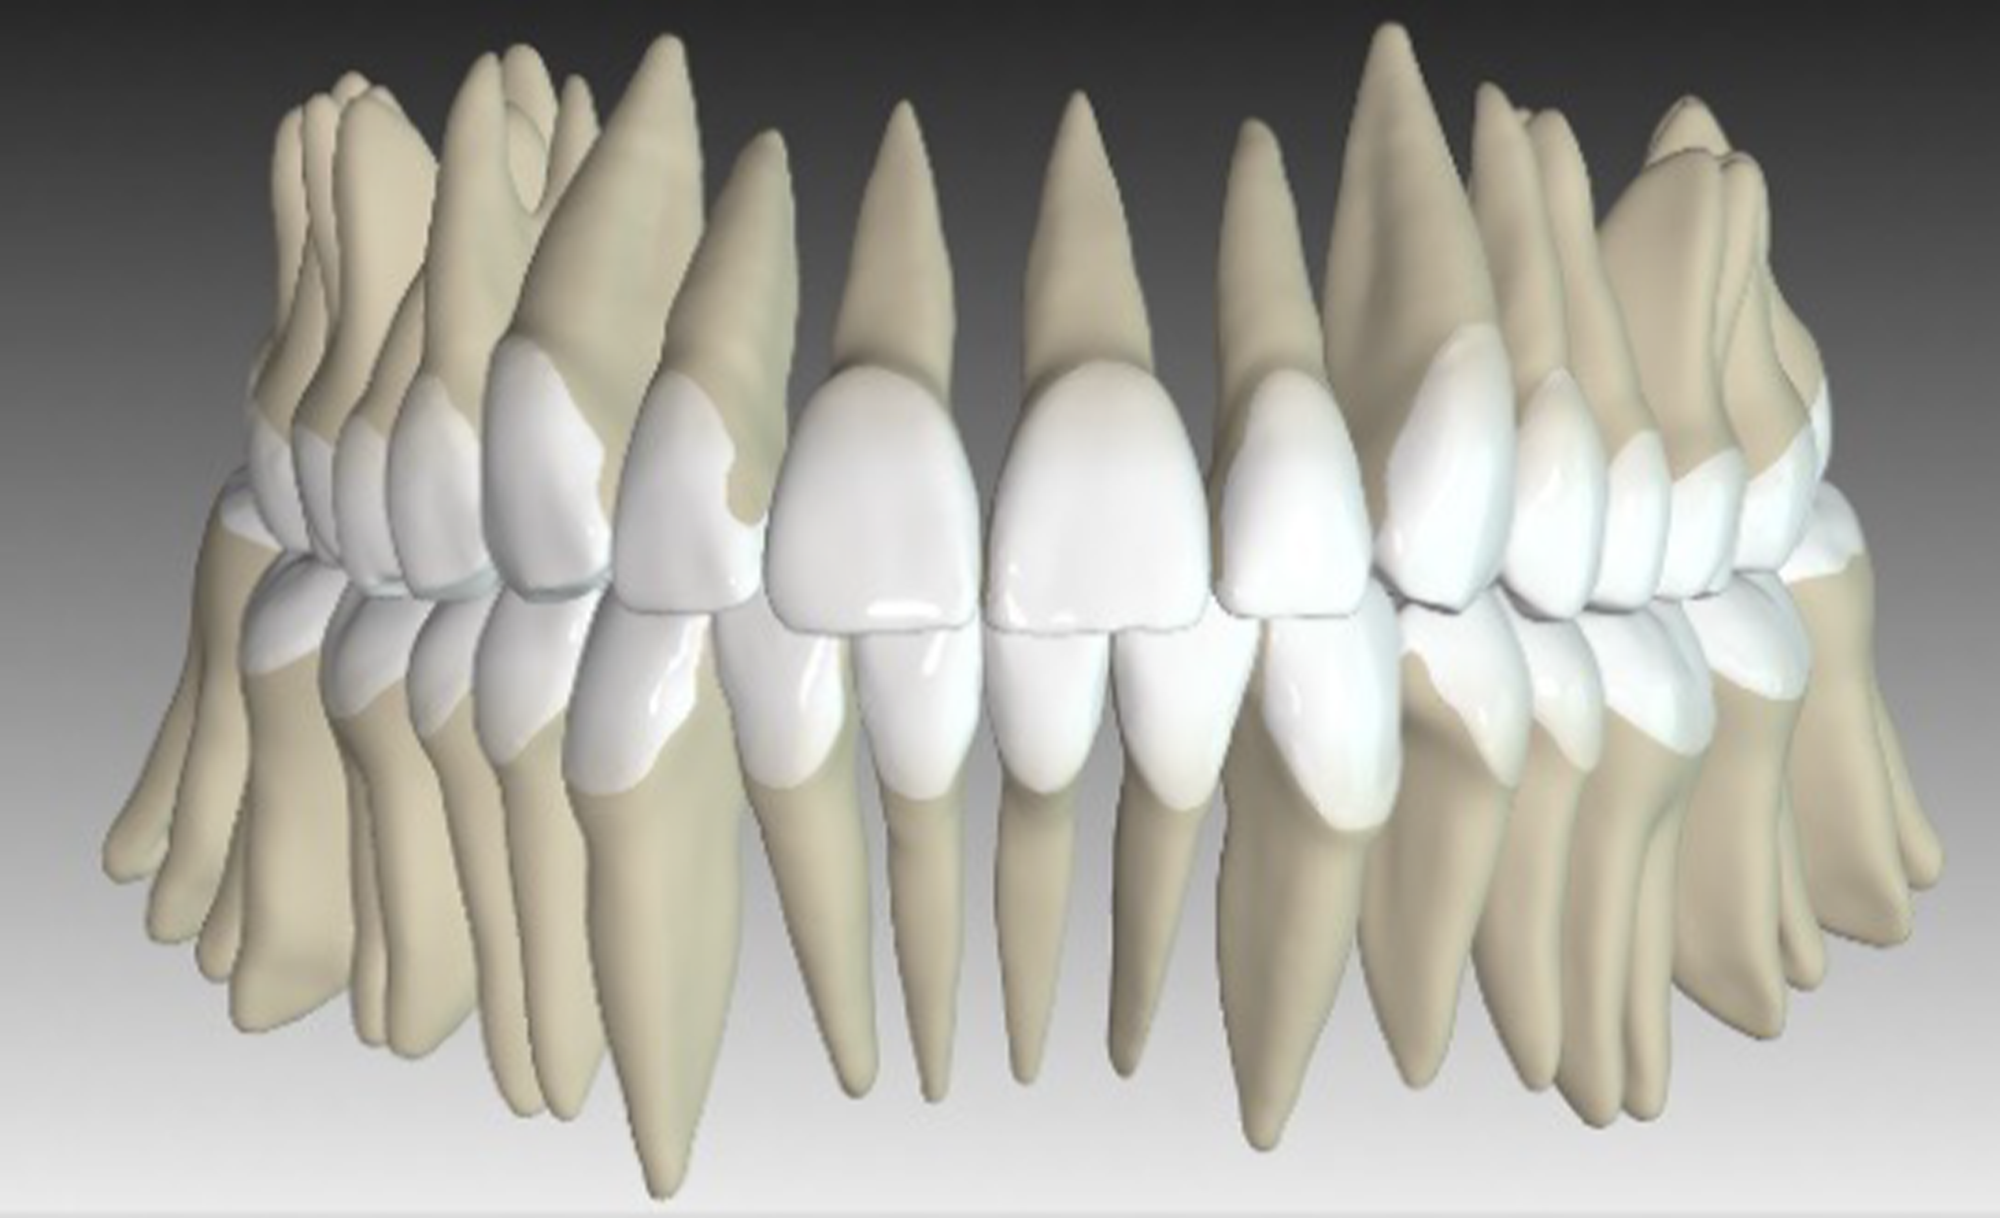

For this purpose, the Approver 3D© software was used, which can simulate not only the movement of the crown, but also the movement of the roots.

20 aligners were planned, along with IPR on lower anterior teeth, of 0.3 mm each. In the upper arch, IPR was avoided by having a slight expansion in the premolar region.

Extrusion of the upper anterior teeth was planned: maximum 2.3 mm in the upper arch and 1.4 mm in the lower arch, using attachments.

As can be seen in the images, the planned vertical correction was fully achieved. It has been noticed that Spark™ Clear Aligners have also helped with the patient’s visceral swallowing pattern, by shielding the tongue which then can no longer (unconsciously) rest between the teeth.